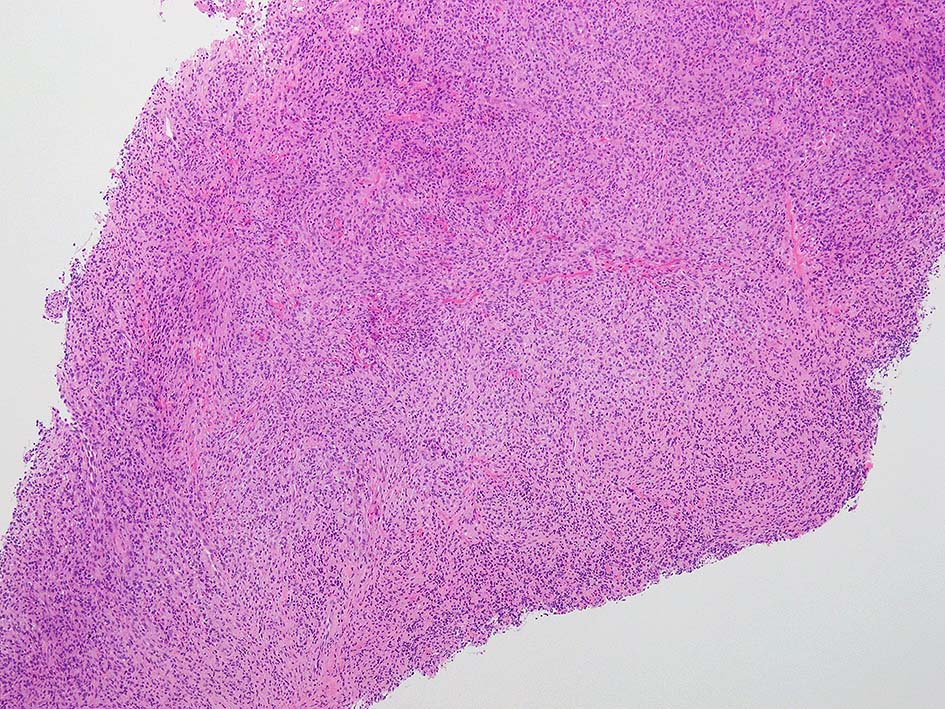

腫瘤組織病理所見

部分生検がおこなわれた.

loupe像:表面に痂皮形成. 均等な組織像で,壊死や出血はみられない. 低倍ではspindle cellの密な増殖があるように見える. 拡大所見では, 類円形, 卵円形, ねじれた桿状の核, くびれ,勾玉様の核など不整形な核をもつ細胞が増殖している. クロマチンは繊細な傾向で, 核小体を1個もつ核が認められる. 高倍率10視野で 1-2個の核分裂像が数えられた.

樹状細胞性腫瘍, 組織球性腫瘍, histiocytic sarcoma(あまり異型がめだたない)などを考えて鑑別, 免疫染色をおこなった.